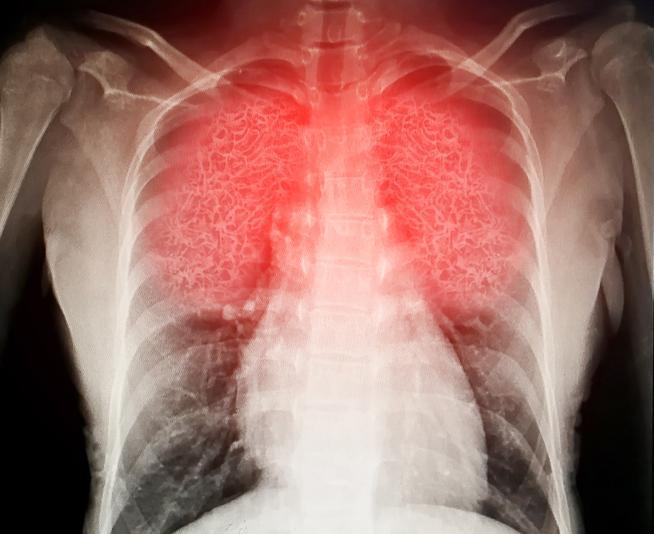

?Zatürrede erken tanı ve tedavi önemli? Zatürrenin tanı yöntemlerine değinen Uzm. Dr. Topal, ?Zatürrede erken tanı ve tedavi büyük öneme sahiptir ve zatürreye bağlı ölümleri azalttığı bilinmektedir. Hastanın yakınmaları zatürreyle uyumlu ise muayene ve akciğer röntgeni tespitiyle genelde teşhis konulabilir. Gerekli durumlarda kan ve balgam tetkikleri yapılabilir? dedi.